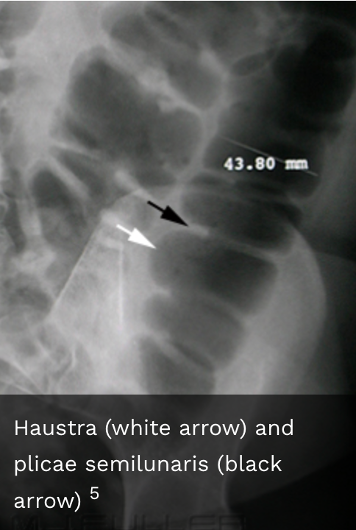

The longitudinal muscles (taenia coli) and circular muscles of the colon form sacculations/pouches called what?

Haustra

What are found in between the haustra?

Plicae semilunaris

Are haustra thicker or thinner than the valvulae conniventes of the small bowel?

Thicker

Do the haustra completely traverse the large bowel

No